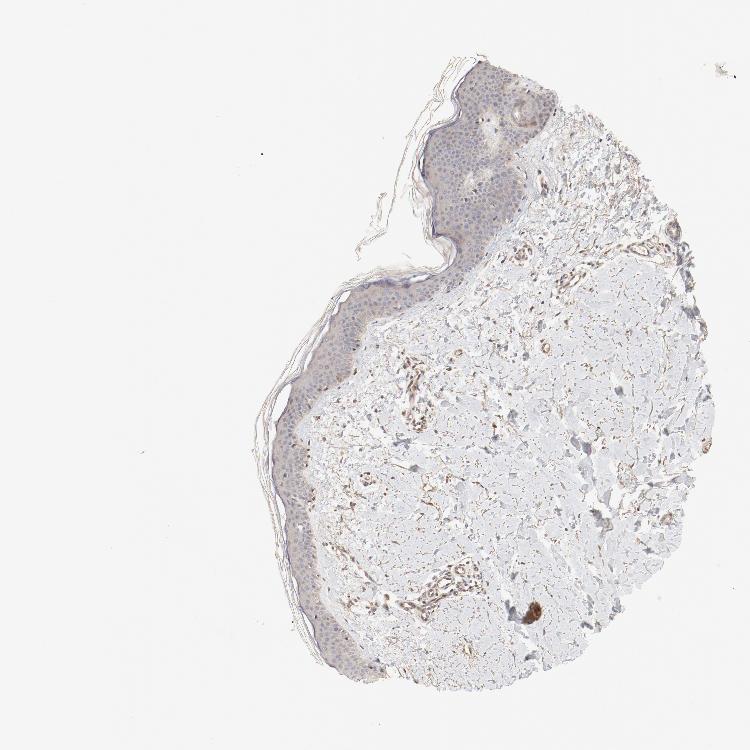

SKIN 2 - Antibody stainingi

Antibody staining in the annotated cell types in the current human tissue is reported as not detected, low, medium, or high, based on conventional immunohistochemistry profiling in selected tissues. This score is based on the combination of the staining intensity and fraction of stained cells.

Each image is clickable and will lead to virtual microscopy that enables deeper exploration of all samples and also displays staining intensity scores, fraction scores and subcellular localization as well as patient and tissue information for each sample.

Antibody HPA003539Antibody CAB018374

Epidermal cells LowLow